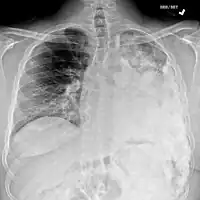

Metastatic osteosarcoma to the left chest -